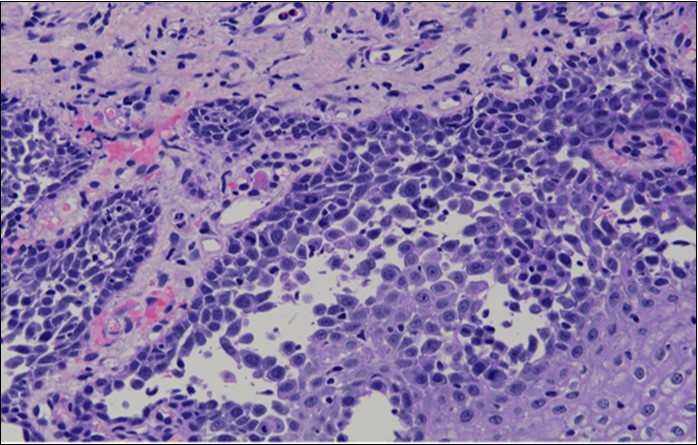

HPV test was negative for high risk subtypes of HPV. The punch biopsy specimen comprised a piece of inflamed cervical tissue in which the transformation zone was represented. The cervical tissue was covered by metaplastic and hyperplastic squamous epithelium showing intraepidermal suprabasal blister formation with acantholysis. Well vascularised dermal papillae lined residual basal cells giving rise to a tombstone appearance were present. There was no evidence of HPV, CIN, CGIN or invasive malignancy.

She was discussed at the hospital cyto-pathology conference to clarify the diagnosis. The original cytological smear specimen was reviewed, with features of bi-nucleation and koilocytosis consistent with LSIL. The cervical biopsy was also reviewed, confirming typical features suggestive of cervical pemphigus. (Figure 4a, Figure 4b, Figure 4c)

Figure 4b.Prominent acantholysis identified

Figure 4c.Well vascularised dermal papillae with residual basal layer giving rise to tombstone appearance